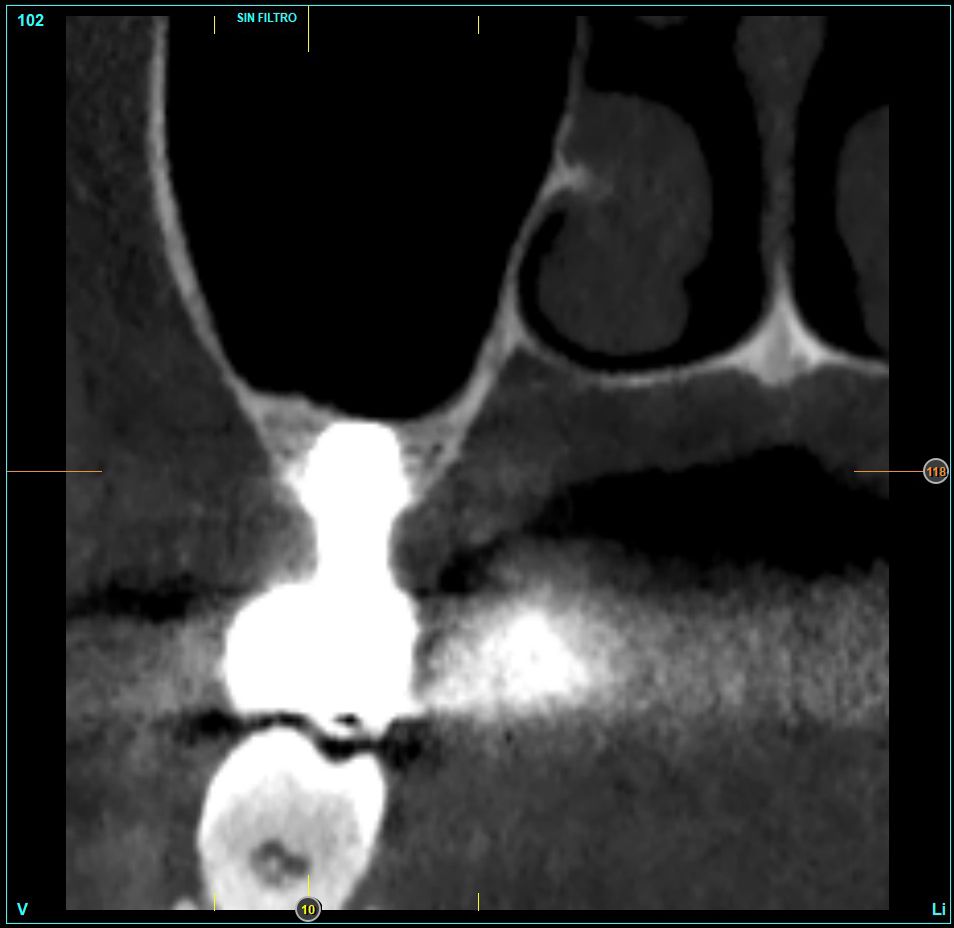

Material and method. A retrospective study has been carried out in patients in whom extra-short implants (4.5 and 5.5 mm length) were inserted directly by transcrestal elevation with residual ridges between 2 and 3 mm. The implant was the analysis unit for the descriptive statistics regarding location, implant dimensions, and radiographic measurements. The patient was the measurement unit for the analysis of age, sex and medical history. The main variable was the gain in height over the apex of the implant after 6 months of the surgery and one year after the load comparing both measurements and as secondary variables the biological complications and the implant failure were recorded.

Results. Ten patients who met the inclusion criteria were recruited and 20 implants were inserted. The mean residual bone volume height was 3.1 mm (+/- 0.3 mm with a range elevation above the apex of the implant in millimetres is of 2.8 mm (+/- 0.99 range 1.9 -5 mm). In the control cone-beam after one year of the studied load of the implants, the bone gain achieved was maintained, with no decrease in the volume gained, only three cases showed a decrease of between 0.4 and 0.5 mm of the initial volume at the end. No implants failed in the follow-up period and no biological complications were found in the surgery.

The crestal lifting technique is currently among the most used to treat the height deficit of the posterior maxilla, when there is a bone remnant of at least 5 mm21-23 in height, although currently there are also research studies that indicate that this technique can be used even if the bone volume is less than this height20-25.

The use of a careful milling technique adapted to the receiving orifice, increasing the primary stability with the diameter of the implant and the anchorage in the vestibular cortex, palatal, mesial and distal (instead of looking for apical anchorage), they are the success keys of these works where extra-short implants have been inserted at residual heights of less than 5 mm even when the residual density was low20-25. In addition, in the follow-up of these implants, no lower success rate or complications related to low residual height or migrations of implants to the maxillary sinus have been 20-25.

In this type of approach to the sinus, an important point is the stability of the grafted bone, located above the apex of the implant and with a bone tissue little vascularized (as usually occurs in these large atrophies with low density), so assessing what happens with the bone volume gained by this long-term procedure is also a key fact26,27. The mineralization of the bone graft and its maintenance once the implant loading is performed can make the difference in the success of the technique, especially in increasingly extreme cases. Therefore, the material used as a graft and the surface of the implant are two factors to take into account when performing this type of procedure28-31. Hydrophilic and osteoconductive surfaces in implants are of vital importance in these complex cases, as well as the filling materials that stimulate the formation of new bone28-31. The implants with UnicCa (Biotechnology Institute, Vitoria, Spain) surface, have a superhydrophilic surface. It is a very rough surface (Optima), with a calcium ions layer. This implies that the contact of blood and plasma with all points of the surface increases to the maximum the active surface for regeneration, by being completely coated with fluids due to its high capillarity. In the following series of clinical cases, patients treated by transcrestal sinus lift, with extra-short and ultra-short implants (4.5 and 5.5 mm), BTI (Biotechnology institute), of internal connection and universal plus platform in residual bone heights below 3 mm, studying the behaviour of implants regarding their survival as well as the maintenance of the bone volume achieved in the crestal elevation.